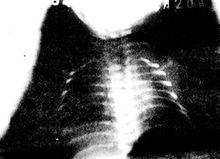

1.胸部X線檢查X線的特徵為兩肺有廣泛蜂窩狀氣囊腫,壁厚,兩肺過度充氣鶒,第Ⅰ、Ⅱ型二肺瀰漫性氣囊腫,兩肺門周圍浸潤鶒,條索影向兩側上、下肺野為融合性氣腫,並有縱隔疝形成,第Ⅲ、Ⅳ型胸片呈小圓形氣囊腫。均有骨質稀疏伴後肋骨多發性骨折